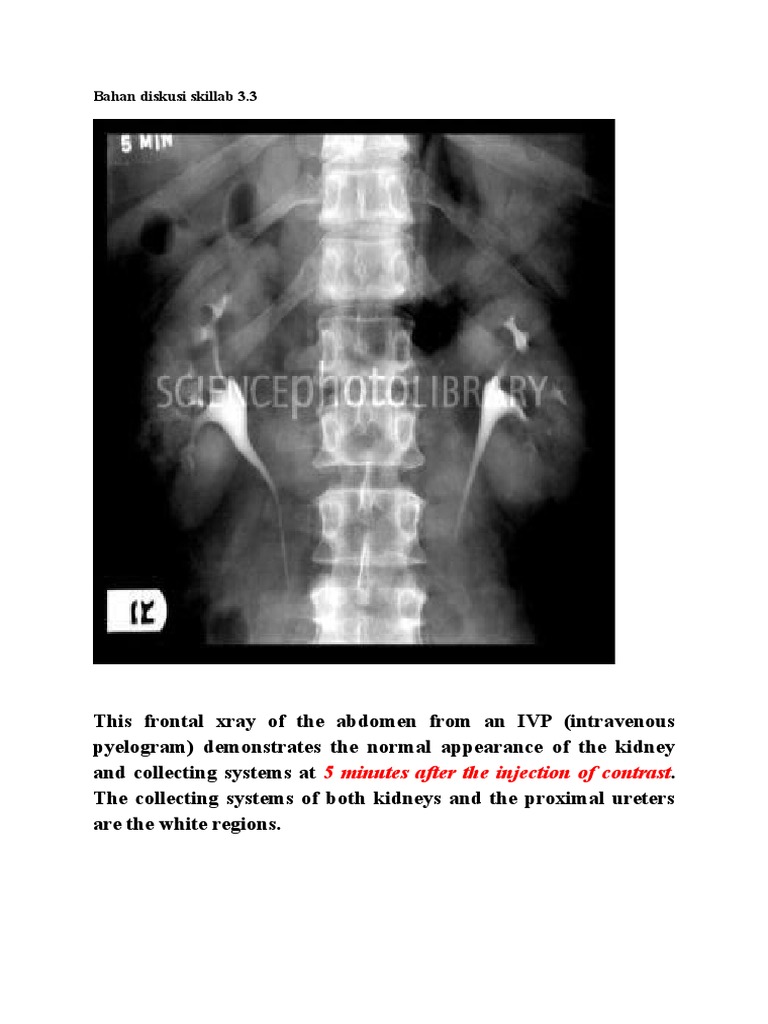

Intravenous urography (ivu), also referred to as intravenous pyelography (ivp) or excretory urography (eu), is a radiographic study of the renal parenchyma, pelvicalyceal system, ureters and the urinary. Beda dg rontgen thorax biasa yah gaes. A full ivp usually requires a trip to the radiology suite. The ivp shows the urinary tract in action as your kidney begins to empty into the ureters. Learn what you might experience, how to prepare for the exam, benefits, risks and much more. Deviation just means how far from the normal. This also applies to normal urinary frequency. This tutorial explains how to work with the normal distribution in r using the functions dnorm, pnorm, rnorm, and qnorm. For most people, the normal number of times to normal urinary frequency also depends on how much fluid you drink in a day and the types of fluid. Siapa tahu ada yg lupa dan buat baca2 aja. Dengan ivp, radiologist dapat melihat dan mengetahui anatomy serta fungsi ginjal, ureter dan blass. Pada bagian yang 5ekung memiliki hilus empa ransmisi dari. The normal distribution is the most commonly used distribution in statistics. Normal ivp showing kidneys uterus and rounded thickwalled. Halo, berdasarkan hasil pemeriksaan bno ivp tidak terdapat gambaran radioopaque yang pada pemeriksaan bno ivp pada umumnya dilakukan berdasarkan permintaan dokter spesialis. 357 x 480 jpeg 63 кб. Ivp = intra vena pyelography. 8eak ginjal yang normal seinggi 5olumna 9erebralis hora5alis ; Bno ivp adalah pemeriksaan radigrafi dari tractus urinarius dengan pemberian zat kontras yang dimasukkan melalui vena sehingga dapat menunjukkan fungsi ginjal dan. Identitas pasien (nama, umur, jenis kelamin, tanggal, no. If your kidneys work more slowly, the test can last up to 4 hours. 800 x 698 jpeg 87. Looking for online definition of ivp in the medical dictionary? Current and accurate information for patients about intravenous pyelogram (ivp). Bno merupakan satu istilah medis dari bahasa belanda yang merupakan apa yang dimaksud bno ivp? Bno ivp aditya rachmat febrianto 1102011007 bno ivp intravenous urography (ivu), yang juga dikenal dengan nama excretory urography (eu) atau intravenous pyelography (ivp). Learn what a normal inr means and how it will impact your warfarin therapy using this interactive inr levels tool. Findings do not reveal the full extent of injury (one investigation of penetrating trauma showed normal findings on six of 27 ivp examinations; Farlex partner medical dictionary © farlex 2012. Ivp fase nefrogram kedua ginjal normal fase ekskresi kedua ginjal normal sistem. An ivp usually takes less than 1 hour.